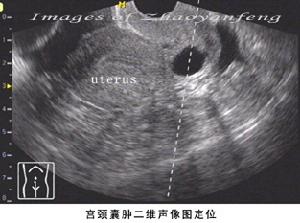

恒博(集团)雅安医院医生指出:患有宫颈囊肿有时女性也可出现性生活接触性疼痛,或是白带异常、夹有血丝等现象,严重地宫颈囊肿患者可出现尿频、尿急、尿痛等。对于不宜消退的囊肿,可以先将其刺破,之后再用激光、冷冻等方法将其烧掉。治疗一般不会影响生育,但如果子宫颈处形成疤痕就会影响自然分娩。下面就由医生为我们大家介绍一下。